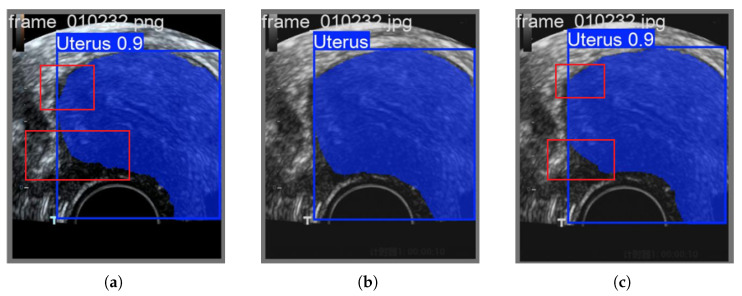

准确识别子宫内膜区域是早期发现子宫内膜病变的关键。然而,目前的检测模型在处理子宫内膜成像数据时仍然面临两大挑战:(1)在复杂和嘈杂的环境中,识别精度仍然有限,部分原因是图像中颜色信息的利用不足;(2)传统的基于二维pca (2DPCA-based)的特征选择方法在捕获和表达子宫内膜区域关键特征方面能力有限。为了解决这些问题,本文提出了一种新的算法,称为特征级图像融合和改进的群体智能优化算法(FLFSI),该算法将学习引导的二进制粒子群优化(BPSO)策略与图像特征选择和重建框架相结合,以增强临床超声图像中子宫内膜区域的检测。具体而言,FLFSI有助于提高特征选择精度和图像重建质量,从而提高区域识别任务的整体性能。首先,我们通过结合结构和颜色信息的特征工程技术增强子宫内膜图像表征,从而提高重建质量并强调关键区域特征。其次,将BPSO算法引入特征选择阶段,提高了特征选择的准确性和全局搜索能力,同时有效降低了冗余特征的影响。在此基础上,对BPSO设计进行了改进,提高了算法的收敛速度和优化效率。本文提出的FLFSI算法可以集成到主流的检测模型中,如YOLO11和YOLOv12。当应用于YOLO11时,FLFSI达到96.6%的Box mAP和87.8%的Mask mAP。利用YOLOv12,进一步将Mask mAP提高到88.8%,表现出优异的跨模型适应性和鲁棒性检测性能。大量的实验结果验证了FLFSI在增强子宫内膜区域检测用于临床超声图像分析方面的有效性和广泛适用性。

Accurate identification of the endometrial region is critical for the early detection of endometrial lesions. However, current detection models still face two major challenges when processing endometrial imaging data: (1) In complex and noisy environments, recognition accuracy remains limited, partly due to the insufficient exploitation of color information within the images; (2) Traditional Two-dimensional PCA-based (2DPCA-based) feature selection methods have limited capacity to capture and represent key characteristics of the endometrial region. To address these challenges, this paper proposes a novel algorithm named Feature-Level Image Fusion and Improved Swarm Intelligence Optimization Algorithm (FLFSI), which integrates a learning guided binary particle swarm optimization (BPSO) strategy with an image feature selection and reconstruction framework to enhance the detection of endometrial regions in clinical ultrasound images. Specifically, FLFSI contributes to improving feature selection accuracy and image reconstruction quality, thereby enhancing the overall performance of region recognition tasks. First, we enhance endometrial image representation by incorporating feature engineering techniques that combine structural and color information, thereby improving reconstruction quality and emphasizing critical regional features. Second, the BPSO algorithm is introduced into the feature selection stage, improving the accuracy of feature selection and its global search ability while effectively reducing the impact of redundant features. Furthermore, we refined the BPSO design to accelerate convergence and enhance optimization efficiency during the selection process. The proposed FLFSI algorithm can be integrated into mainstream detection models such as YOLO11 and YOLOv12. When applied to YOLO11, FLFSI achieves 96.6% Box mAP and 87.8% Mask mAP. With YOLOv12, it further improves the Mask mAP to 88.8%, demonstrating excellent cross-model adaptability and robust detection performance. Extensive experimental results validate the effectiveness and broad applicability of FLFSI in enhancing endometrial region detection for clinical ultrasound image analysis.